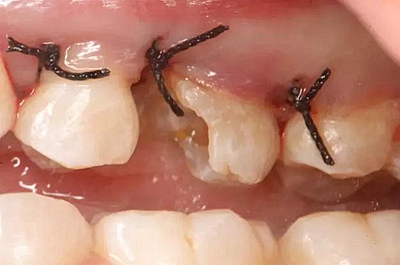

患牙遠(yuǎn)中邊緣嵴完整,強(qiáng)度沒(méi)有降低,故擬保留遠(yuǎn)中邊緣嵴,高嵌體修復(fù)。首先去除腐質(zhì)及原墊底材料,流體樹脂+3M Z350XT樹脂墊底。局麻下行冠延長(zhǎng)手術(shù)。在此需要提及個(gè)人的一個(gè)觀點(diǎn)。冠延長(zhǎng)手術(shù)原則上要求3-6個(gè)月以上才能永久修復(fù)。但是個(gè)人喜歡后牙肩臺(tái)建立在齦上,所以修復(fù)后的修復(fù)體邊緣位于牙齦上方1mm,對(duì)牙周的愈合影響較?。ㄈ绻麨辇l下邊緣則要慎重),故該患者術(shù)中按照齦上邊緣的設(shè)計(jì)進(jìn)行冠延長(zhǎng)手術(shù)。以下為術(shù)中:

改良垂直褥式縫合關(guān)閉傷口,傷口無(wú)明顯滲血,高嵌體預(yù)備完畢后,硅橡膠取模,見邊緣清晰。灌注模型,模型上3MZ350XT分層堆塑高嵌體。